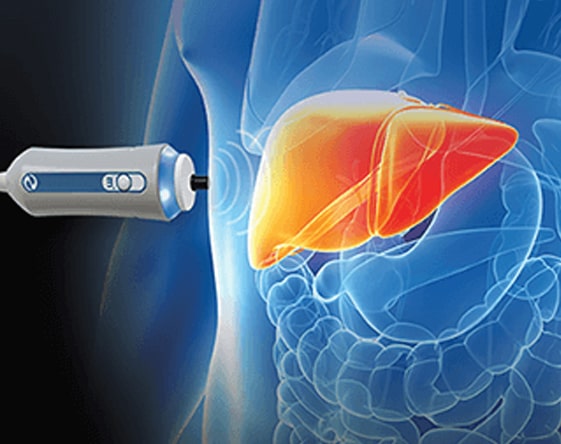

Liver Elastography

Diagnosis & assessment of chronic liver disease. It is a non-invasive medical imaging...

Read More